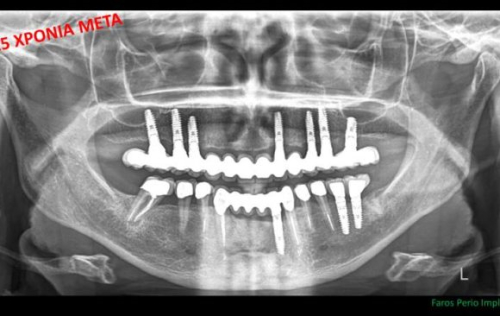

Τα Οδοντικά Εμφυτεύματα χρειάζονται συντήρηση, όπως και τα Δόντια μας

Τα οδοντικά εμφυτεύματα στα στόματα Ελλήνων ασθενών αυξάνονται σε καθημερινή βάση. Τι πρέπει όμως να γνωρίζουμε και να προσέχουμε ώστε...